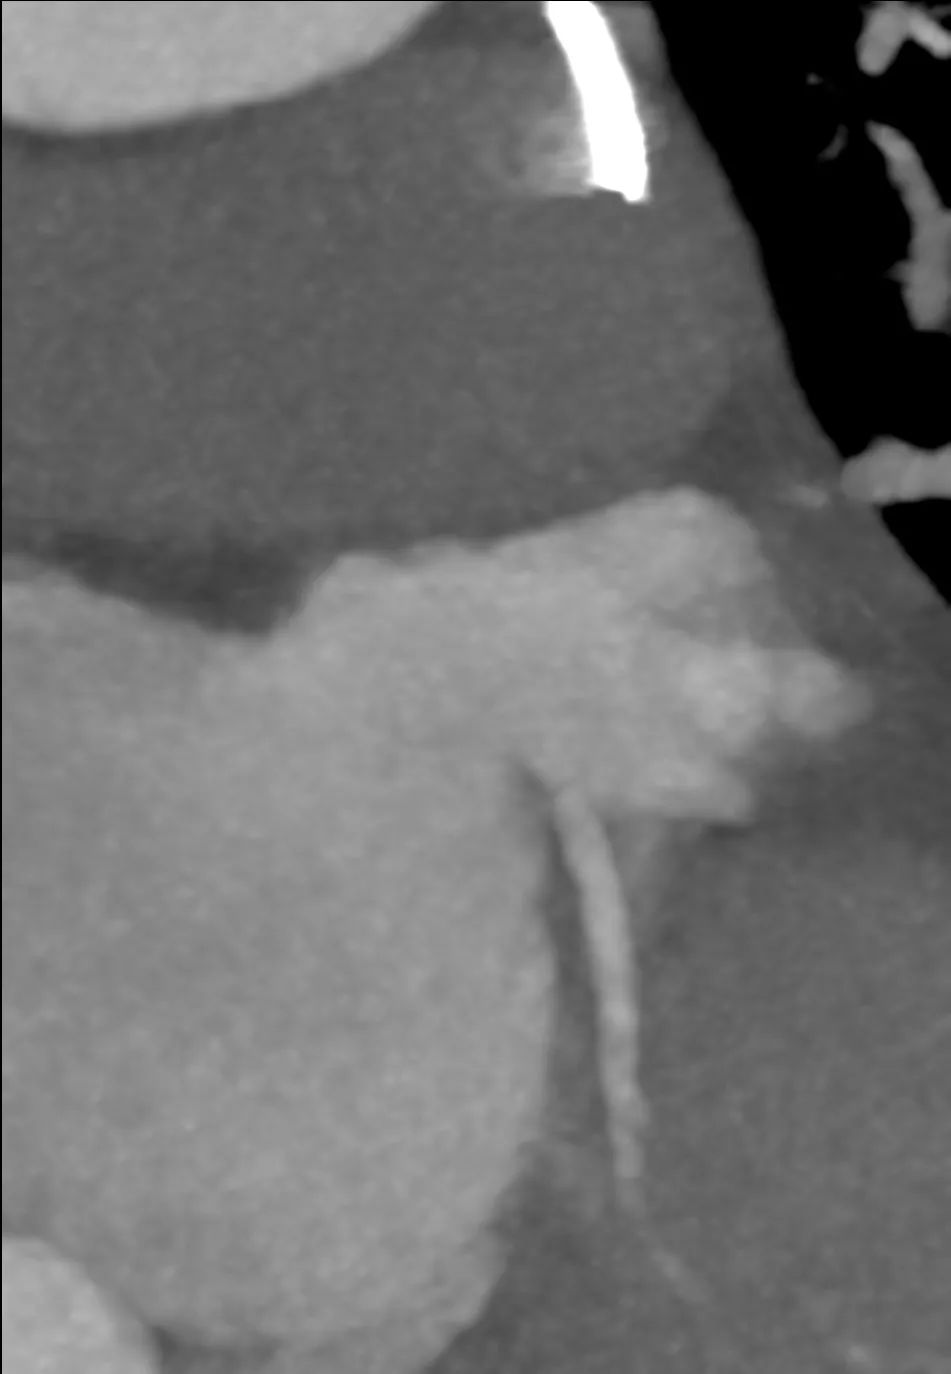

瓣膜内22mm球囊后扩张,左冠无显影

LM烟囱支架植入4.0*30mm